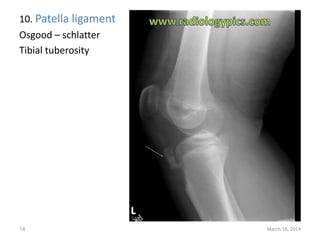

The document lists 10 common sites of avulsion fractures caused by the tearing away of tendons or ligaments from bone. It identifies the specific muscles or tendons that can cause avulsion fractures at the iliac crest, ischial tuberosity, greater trochanter, lesser trochanter, posterior calcaneus, olecranon process, superior patella, inferior patella, and tibial tuberosity.